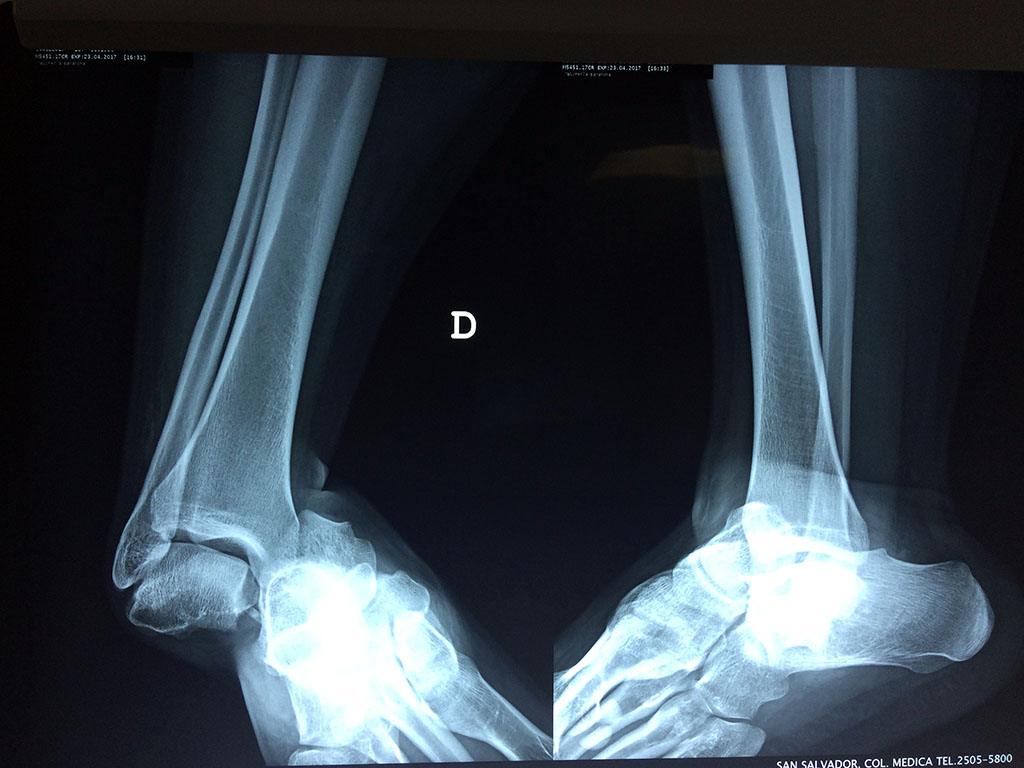

Algunas fracturas de tobillo pueden requerir cirugía si:

- Los extremos de los huesos están desalineados entre sí (desplazados).

- La fractura se extiende hasta la articulación del tobillo (fractura intra-articular).

- Los tendones o ligamentos (tejidos que sujetan los músculos y los huesos entre sí) están rotos.

- El médico cree que sus huesos probablemente no sanen apropiadamente sin cirugía.

- El médico considera que la cirugía puede permitirle una recuperación más rápida y confiable.

Cuando se necesita cirugía, es probable que esta implique el uso de clavijas de metal, tornillos o placas para sostener los huesos en su lugar mientras la fractura se consolida. Los elementos de soporte pueden ser temporales o permanentes.